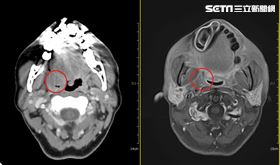

人夫包莖封死30年!醫驚:整圈都是硬塊

有私密處困擾應盡早解決。亞洲大學附屬醫院男性性功能中...